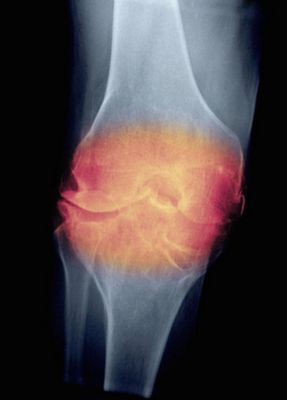

«В северных широтах существует более высокий риск», сказал доктор Виейра. «Это могло бы быть связано с фактом, что существует меньше солнечного света в этих областях, приводящего к дефициту витамина D».Исследование посмотрело на данные от медицинского Исследования Медсестер, долгосрочного когортного исследования американских медсестер. Смотря на адреса места жительства, последствия для здоровья и поведенческие факторы риска для участников между 1988 и 2002, исследователи основались свои результаты исследования на 461 женщине, у которых был РА, по сравнению с многочисленной контрольной группой 9 220.РА является хроническим воспалительным заболеванием, влияющим на покров суставов, главным образом в руках и коленях.

Этот хронический артрит характеризуется путем набухания и краснота и может стереть хрящ между костями. РА в два – три раза более распространен в женщинах, чем в мужчинах.